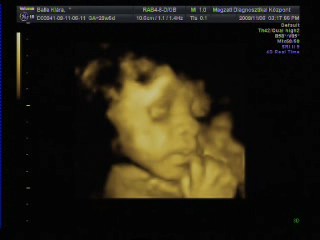

Athena, Jutka. Nilszi-nek igaza van abban, hogy sokszor nem mérnek pontosan az UH-k alkalmával. Misem bizonyítja ezt jobban , mint az én esetem. Szerdán este a rendeléses Uh-n , ahol elég lelkiismeretesen mért a szonográfusnő, ott a picur méretét: 1518g-ra becsülték ( kicsit meg is ijedtem!) A pocakja szép nagy volt AC:255mm a combcsontja, amire kétszer is rámért FL:53mm, BPD( fejátmérő):75mm HC ( fejkörfogat):266mm.

Másnap reggel mentem 4D UH-ra, ahol BPD: 72,6mm HC: 261,9mm AC: 220,2mm FL: 57,5mm becsült súly: 1108g.

Pedig ugyan arról a gyerekről van szó!!!! Nem hiszen, hogy lüktetne a pocakomban. :lol:

Hát ennyit a gépekről és a pontos méretekről!!!

Ráadásul képzeljétek hogy jártam a 4D UH-n. Zsomborka egyáltalán nem akarta megmutatni magát, nem fordult be a gerincem felé néz és annyira betakarta a karjával és a felhúzott lábacskáival magát, hogy semmit nem lehetett látni belőle. Hiába forogtam, mozgattuk a pocakom, fel sem ébredt és egyáltalán nem akart elmozdulni.

Egyetlen képet tudott csak készíteni a szonográfus, azt is csak a talpacskájáról. Nagyon csalódott voltam, mert ugye azt már tudtam, hogy egészséges nincs semmi baja, mert azt már előző nap megnézték, most csak őt szerettük volna látni. Így nagy nehezen kikönyörögtem, hogy nem jöhetnék-e vissza, hátha fordul egy kicsit. Kora délutánra kaptam még egy időpontot. Persze mondanom sem kell, hogy otthon még bukfenceztem is, hogy egy kicsit elforduljon, csokit ettem, kávét ittam ( pedig soha nem iszom )

A babóca mégsem akart elmozdulni, már majdnem azt mondta a szonográfus, hogy csinál egy képet, de hagyjuk a DVD-t mert most sem látszik semmi, mikor egyszer csak mintha halotta volna Zsimbi mégiscsak fordult egy kicsit, hogy végre szülei megcsodálhassák. Persze a kép szemcsés volt és még így is betakart a kis kezecskéje egy kicsit, de mi olyan boldogok voltunk, hogy végre látunk belőle valamit, hogy madarat lehetett volna fogatni velünk. Sőt még ásított is egyet, biztos érezte, mekkora a sikere, annak, ha kicsit produkálja magát. Így végre meg lett a várva várt DVD. Sajnos képet nem tudok róla berakni, mert a laptop-om nem szereti ezt a DVD-t és nem akarja elindítani, így csak a lejátszónkon tudom megnézni, de ott nem tudok képeket kivágni. Így csak egy képet tudok bescannel-ni, amit az Uh-osok nyomtattak ki fekete fehérben.

Kép Zsomborka 28+4

Kép Zsimbi talpacska